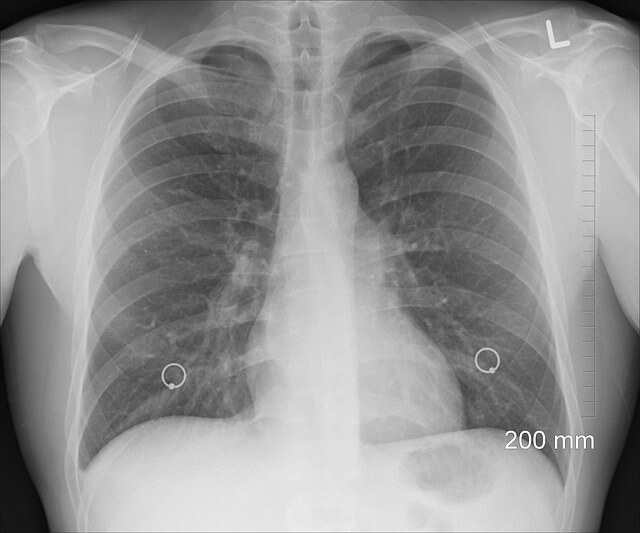

폐에 물이 차는 원인에 따른 치료 방법

폐에 물이 차는 원인에 따라 치료 방법이 달라질 수 있습니다. 대표적인 치료법을 살펴보겠습니다.

| 치료 방법 | 설명 | 비고 |

|---|---|---|

| 이뇨제 투여 | 체내 과도한 수분을 배출하여 폐부종을 완화 | 심부전 환자에게 효과적 |

| 산소 치료 | 산소 공급을 통해 호흡곤란 완화 | 응급 상황에서 필수 |

| 흉강천자 | 바늘을 이용해 흉막삼출액을 제거하여 호흡 개선 | 일시적인 해결책 |

| 항생제 치료 | 폐렴이나 감염으로 인한 경우 항생제 치료 진행 | 세균 감염 시 필수 |